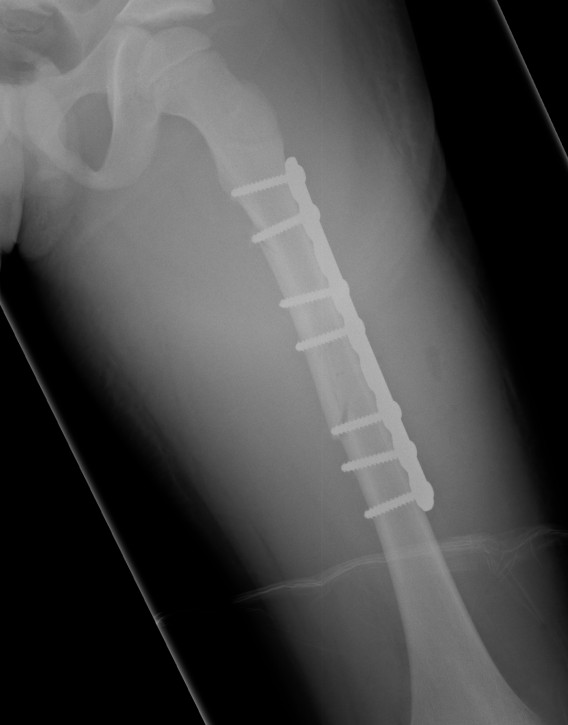

Plate

Indication

- length unstable fractures (spiral / comminuted)

- very distal or proximal fractures

Options

1. Open Plating

2. Submuscular bridge plating

Technique

- supine on radiolucent table or traction table

- incision 5cm proximal or distal (depending # site)

- blunt dissection to periosteal layer

- run bristow or cobb elevator submuscularly

- 3.5 or 4.5mm LCP plate (depending on patient size and age)

- place plate submuscularly

- use stab incisions to place 3 screws above /below fracture

- sufficient spread

Postop

- TWB / PWB for 6/52 until union

- removal at 6/12